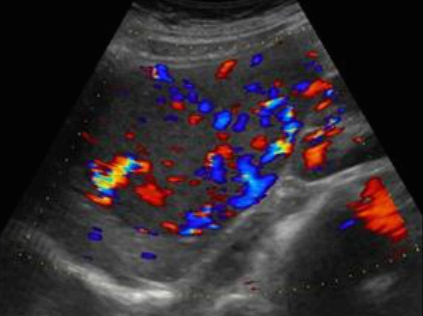

FNH의 경우 초음파소견은 다양하다. 병변은 등에코, 저에코, 고에코의 균질한 덩어리로 나타날 수 있다. 간내 혈관을 대체할 수 있는 대량 효과가 있다. 단지 18%의 사례에서만 중앙 흉터(저에코성 센터)가 존재한다. 이는 간혈관종과 매우 유사해 보인다. 또한 혈관 기형부위와 관련이 있다. 일반적으로 5cm 미만이다.

FNH (Focal Nodular hyperplasia) US finding

- spokewheel vascularity

- iso-hyperechoic mass

- hypoechoic lesion with central scar

- fatty liver

- isoechoic lesion

- central feeding artery

위에서 보인 초음파소견처럼 FNH는 경계가 명확한 균일한 종괴이며 내부에 섬유성 반흔이 있다. 에코는 저에코를 갖지만 간혹 고에코나 등에코등 다양하게 나타날 수 있으며 피막이 없다. 도플러상 과혈관성을 보이며 정상 간세포조직을 갖는다. 초음파 만으로 간암과 구별할 수 없으므로 혈액검사, CT 와같이 다양한 검사를 통한 진단이 필요하다.